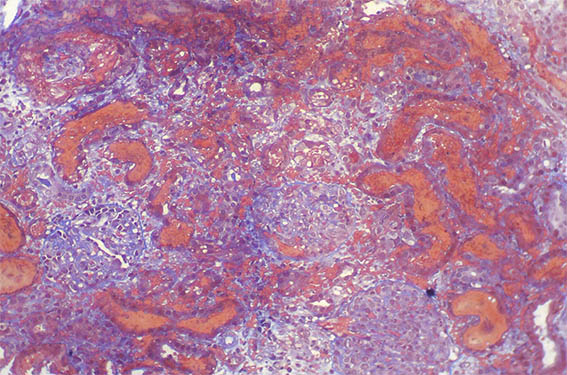

Figure 1.

H&E, X100.